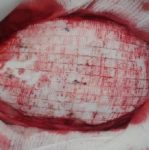

během operace

Operace trvala 3,5 hodiny. Implantace protézy Codubix® CT samotné trvala zhruba 30 minut.

6. Hodnocení lékaře